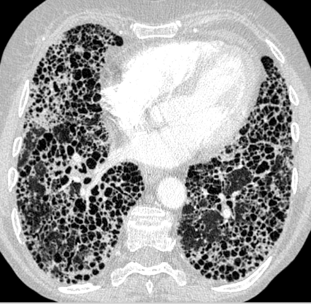

- High resolution CT scan: this is the best way to detect ild: will see a reticular pattern, opacities, and honeycombing

- High-resolution CT scan will show honeycombing

- Honeycombing on CT scan